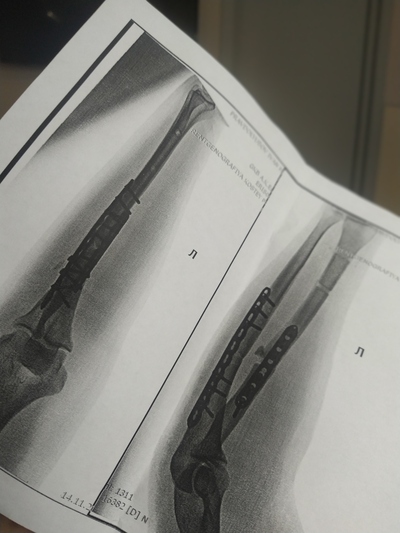

У меня оскольчатый фрагментарный перелом диафиза бедра со смещением отломков. Шрамов теперь ояебу. Помимо шрама на ноге, шрам от полостной операции на животе, страшенные шрамы на коленях, на плече, на боках. Так что, у тебя ещё не так всё плохо:) мне всё тело забивать тату придётся